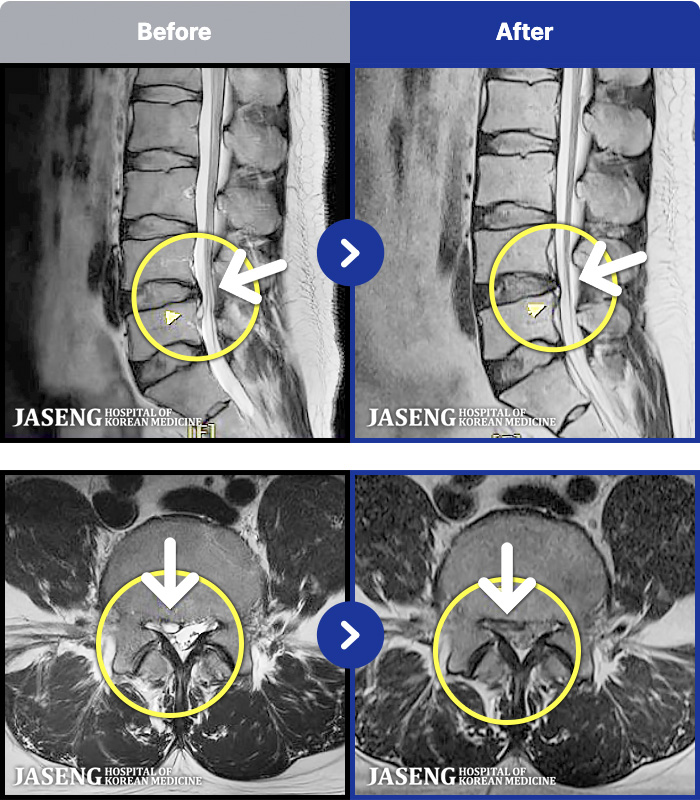

- MRI ġ

MRI ġ

1,304 MRI ũ ʸ Ȯϼ.